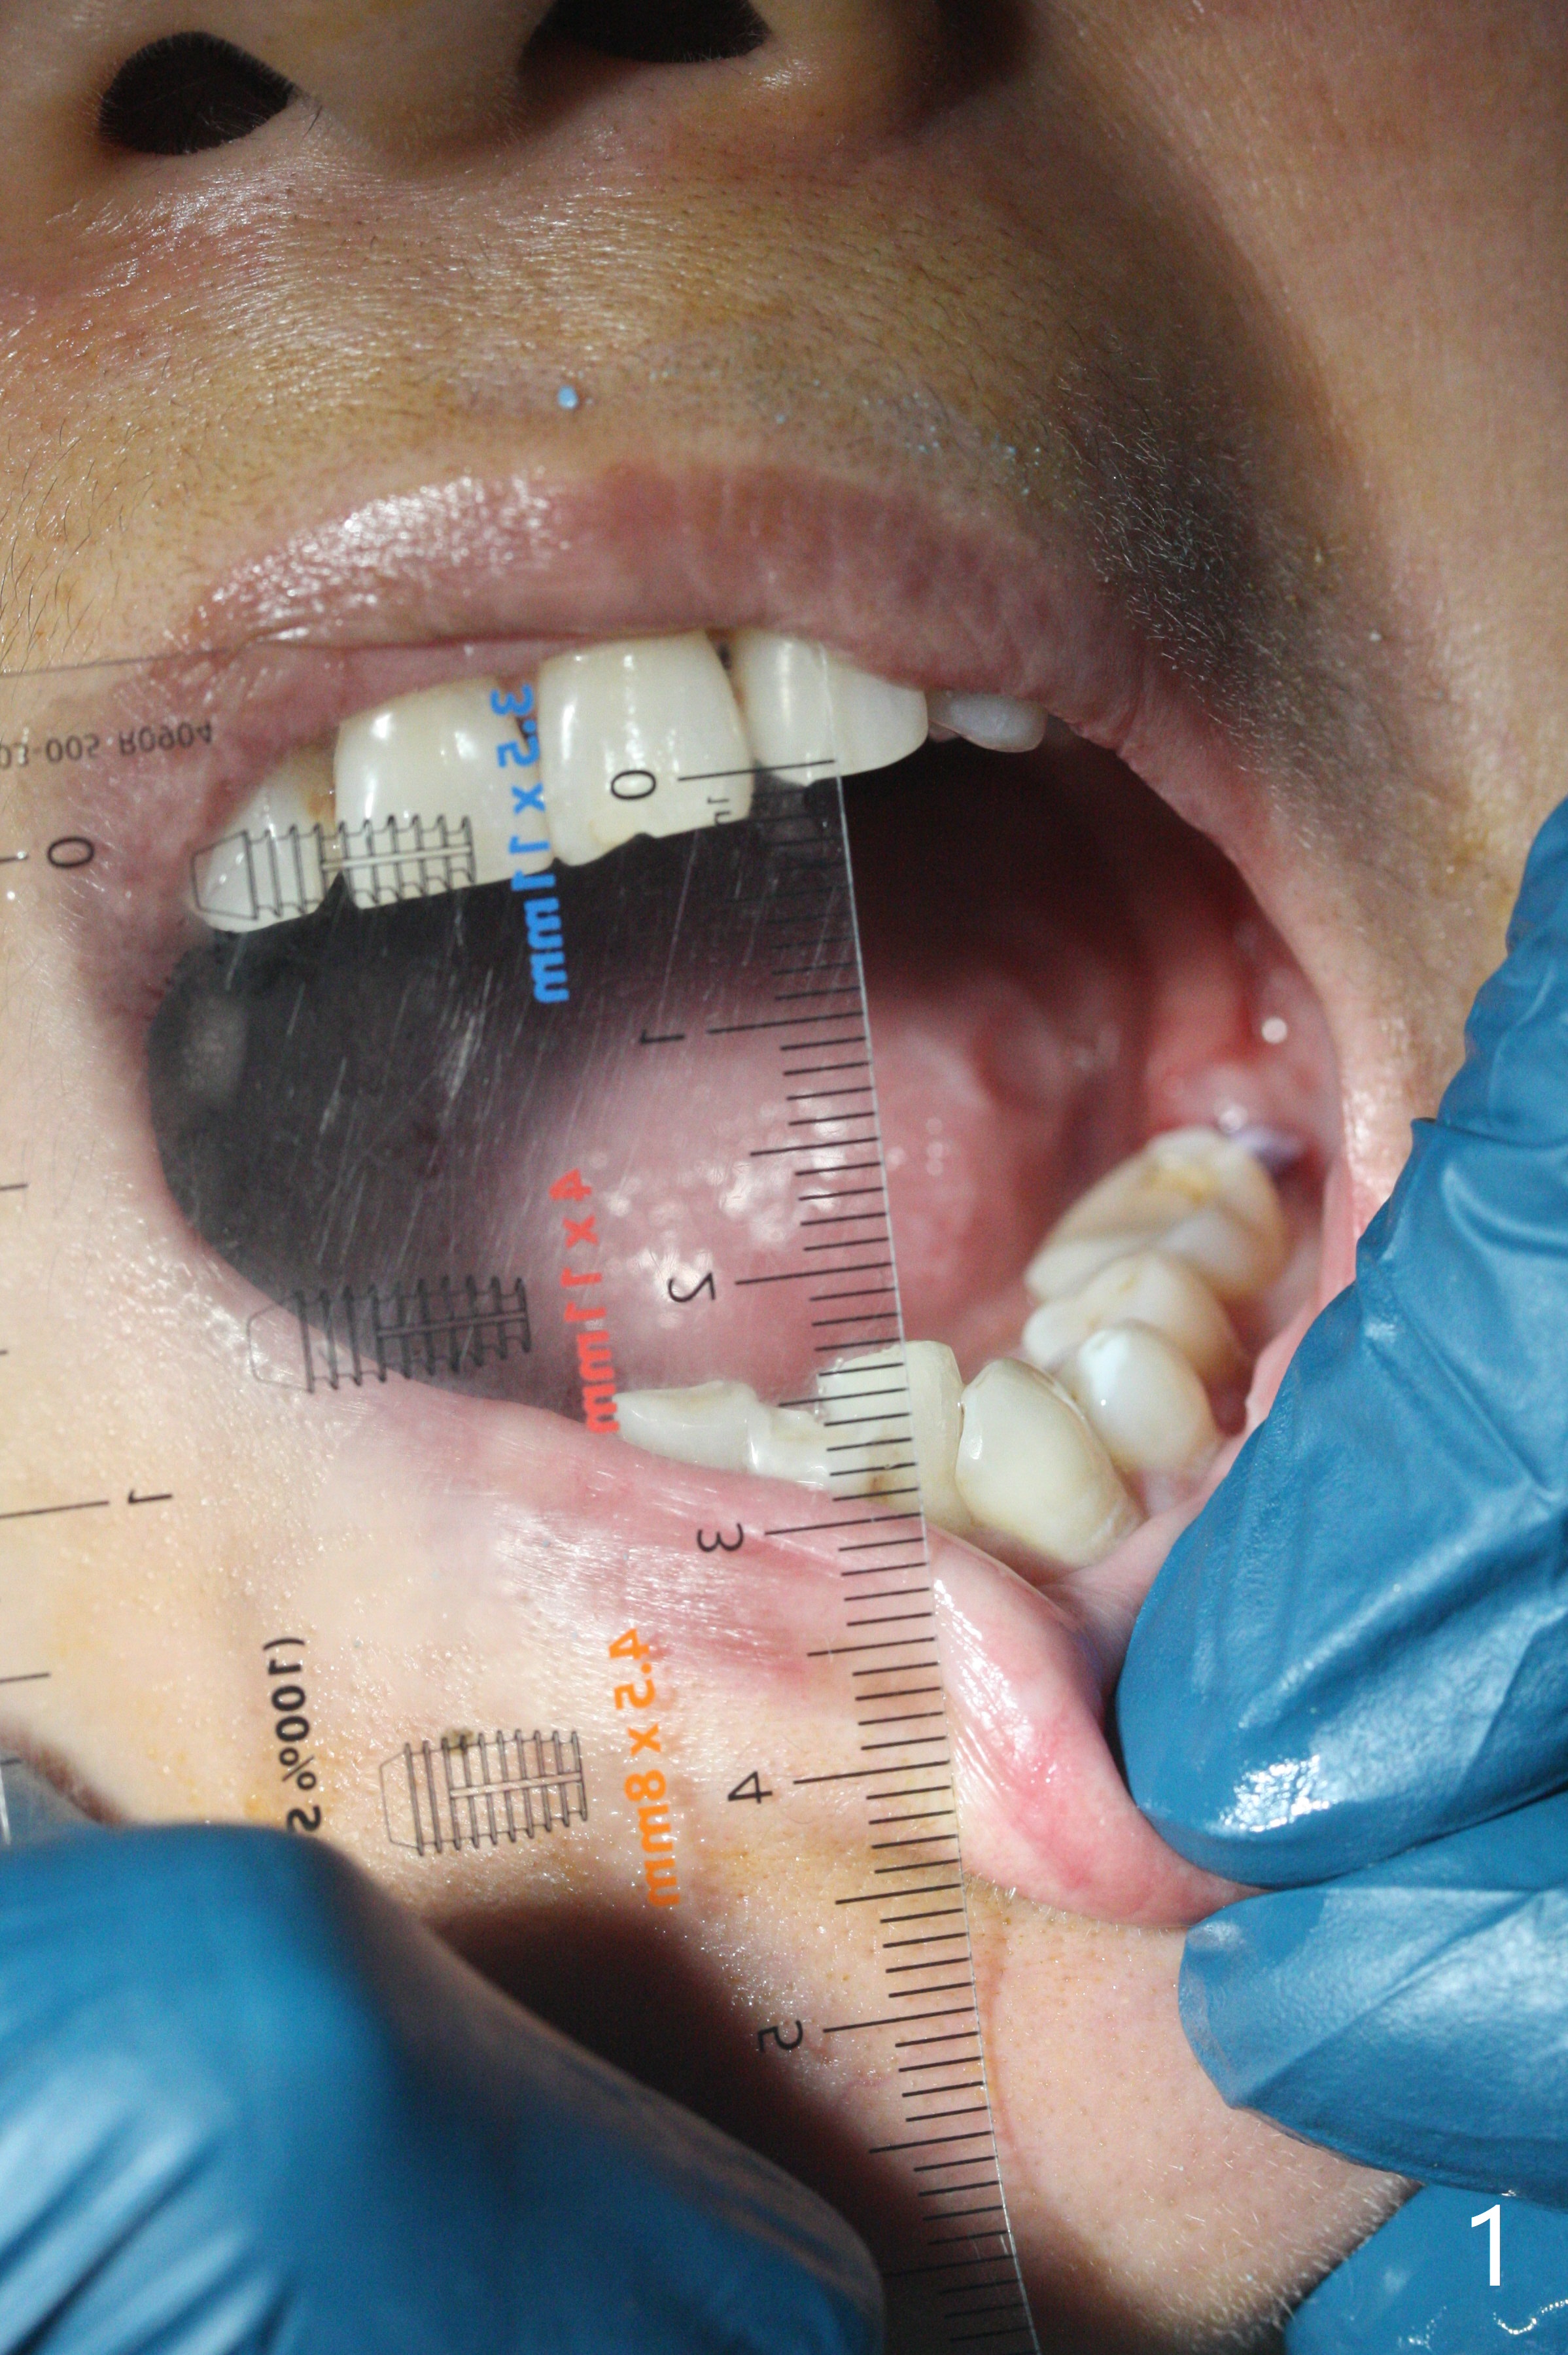

今天手术病人57岁,女,拔除左下第二磨牙后,左侧颞颌关节症状加剧,病人坚信植牙是解决途径,愿意配合。导航取模后,推荐night guard,不接受,但是她开始服用肌肉松弛剂(Cyclobenzaprine (Flexeril)),晚上睡觉好,但是她认为药物对张口度没有帮助。尽管如此,她虽然胆小,还是勇敢回来植牙。其实取模前并没有测量张口度,但是感觉没什么问题。术前测量25 毫米(图一),据说45毫米才能使用导航,抱着车到山前必有路想法,就踏上愉快行程,其实病人后牙特别短,后牙上下颌垂直距离还够,所以第一个钻头没问题,一路顺风。当植体与driver结合后,就是不能插入导板。当取下导板,将三者一起放入口腔,植体却掉入口腔,快进入咽腔。经过反复尝试,安全步骤是:首先徒手初步植入植体,然后将导板,driver和扳手(torque wrench)一起放入口腔(图二),反复确定导板和driver就位,最后使用扳手,将植体植入巧好的深度(图三)。总之,问题都有解决办法。